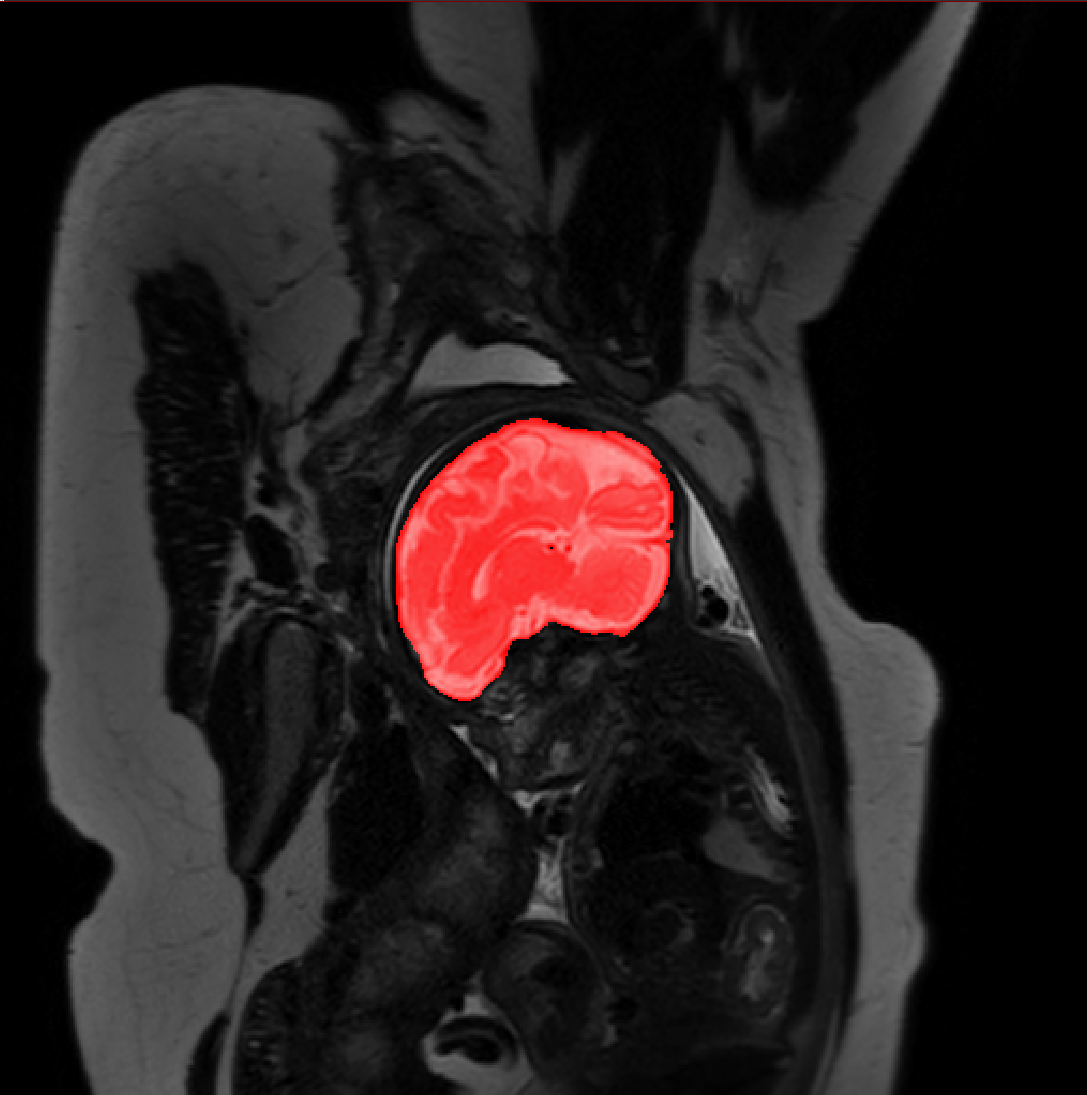

Table 1 lists average of quantitative evaluation results of these experiments and Figure 2 shows results obtained from each image. Figure 3 shows examples of the obtained segmentations.

Refer to caption

Figure 3: Example of ICV segmentations in images acquired in axial (left), coronal (middle) and sagittal (right) planes. Top row: A slice from T2-weigted image; Second row: Automatic segmentations obtained using 7 training images from the representative imaging planes; Third row: Automatic segmentations obtained using all 21 training images from all 3 image orientations; Bottom row: Manual segmentation.